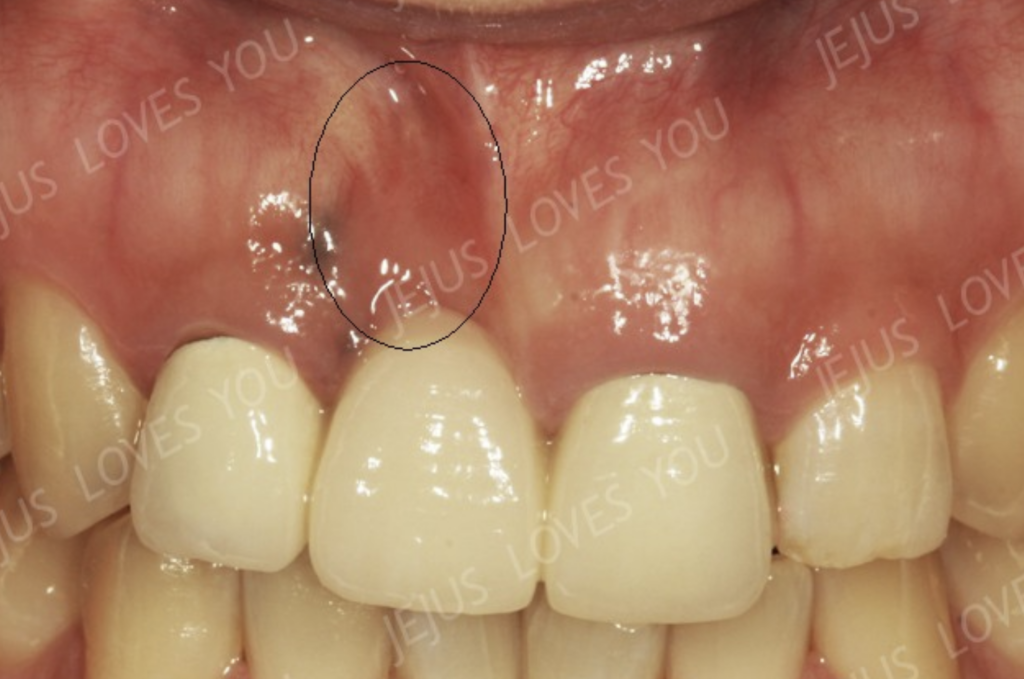

얇아진 뼈의 자리에 동그라미 표시를 해 두었습니다. 처음 휴먼브릿지나 메릴랜드를 하실 때에는 지금 사진의 치아처럼 치아가 길어지지는 않을 수 있지만 시간이 지나면서 해당 부위가 꺼지면 음식물이 끼일 수 있어서 이렇게 치아를 길게 만드는 형태로 계속적인 수리를 보게 됩니다.

위의 환자의 스마일사진입니다. 브릿지로 치료할 경우 이렇게 웃을 때 잇몸이 많이 보이기라도 할 경우라면 화살표 부분처럼 그림자가 지게 됩니다.

또다른 환자 한 분의 스마일을 보아도 마찬가지로 브릿지로 해결한 빠진치아부위에 그림자가 있습니다. 다행히 웃는 라인이 많이 올라가지 않지만 그래도 티는 납니다.

브릿지로 치료하게 되시면 어금니는 몰라도 특히 앞니 부위에서는 약간의 뼈소실이라도 있게 되면 스마일을 하실 때 치아와 잇몸경계부위에 어두운 그림자가 지게 됩니다. 이는 휴먼브릿지나 메릴랜드도 마찬가지입니다. 물론 치료직후부터 그런 현상이 두드러지지는 않지만 1년, 2년이 지나면서 점점 더 뼈소실양은 늘어가고 그림자는 뚜렷하게 형성될 수 있습니다.